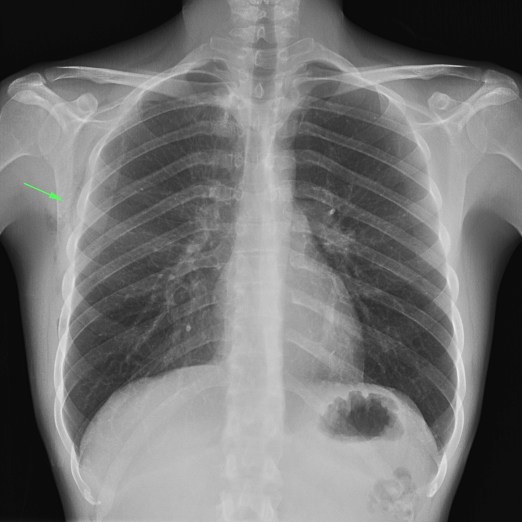

Mismo paciente, al cual esta vez se le ha tomado una radiografía en PA y en sedestación. Observar como las clavículas están equidistantes a las apófisis espinosas y como ha desaparecido el velamiento del pulmón izquierdo.

Por otra parte, paciente presenta una cardiomegalia y un discreto ensanchamiento del mediastino es probable relación con cambios postquirúrgicos.